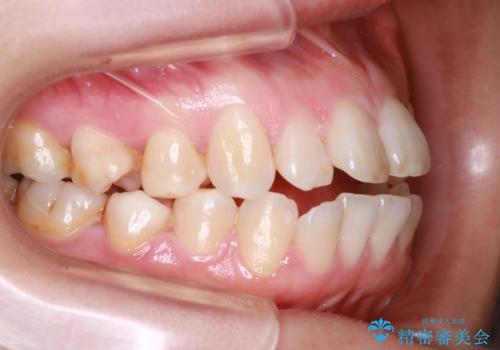

- 前歯のでこぼこが気になると来院されました。

奥歯の噛み合わせは綺麗に噛んでいたため、前歯の叢生(でこぼこ)を、短期間で治療完了するように計画しました。

前歯のガタツキを改善する治療法として、マウスピース矯正が適していることが多いです。

マウスピース矯正は、金属製のブラケットやワイヤーを使用せずに、透明なマウスピースを装着して歯を移動させる方法です。そのため、目立たず、痛みも少ないです。